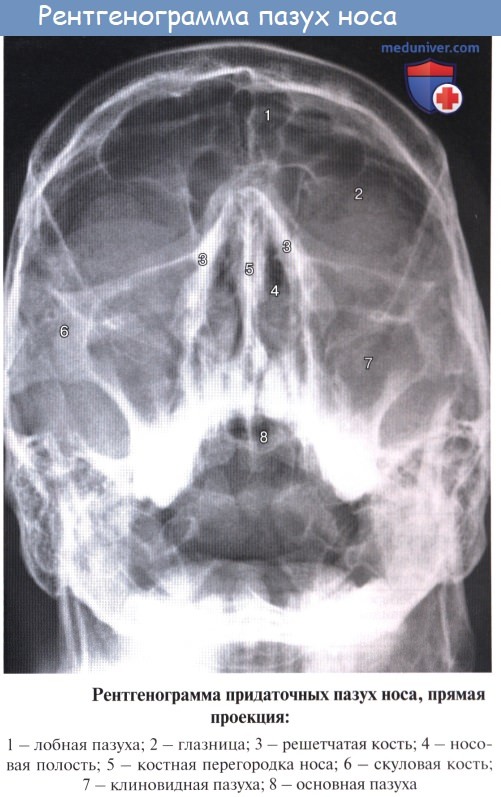

Дополнительным приспособлением для вентиляции воздуха служат околоносовые пазухи, sinus paranasales, также выстланные слизистой оболочкой, являющейся непосредственным продолжением слизистой носа. Это описанные в «Остеологии»:

1) верхнечелюстная (гайморова) пазуха, sinus maxillaris; широкое на скелетированном черепе отверстие гайморовой пазухи закрывается слизистой оболочкой, за исключением небольшой щели;

2) лобная пазуха, sinus frontalis;

3) ячейки решетчатой кости, cellulae ethmoidales, составляющие в целом sinus ethmoidalis;

4) клиновидная пазуха, sinus sphenoidalis.

При осмотре носовой полости у живого (риноскопия) слизистая оболочка имеет розовую окраску. Видны носовые раковины, носовые ходы, ячейки решетчатой кости и отверстия лобной и верхнечелюстной пазух. Наличие носовых раковин и околоносовых пазух увеличивает поверхность слизистой оболочки, соприкосновение с которой способствует лучшей обработке вдыхаемого воздуха. Свободная циркуляция воздуха, необходимого для дыхания, обеспечивается неподатливостью стенок носовой полости, состоящей из костей (см. «Остеология»), дополняемых гиалиновыми хрящами.

С каждой стороны к полости носа примыкают верхнечелюстная и лобная пазухи, решетчатый лабиринт и отчасти клиновидная пазуха.